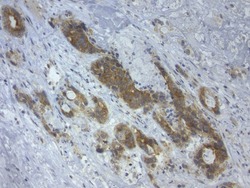

- Immunohistochemical staining of paraffin-embedded human colon cancer using mouse anti-LGR5 clone UMAB212 (UM800104) at 1:400 with GBI Polink2 Broad HRP DAB detection kit (D22-110); pretreatment of tissue prior to stain with heat-induced epitope retrieval buffer from GBI Labs TEE pH 9.0 (B21-100)using pressure chamber for 3 minutes at 110°C is required for optimal staining. Shown here strong cytoplamic tumor cells.